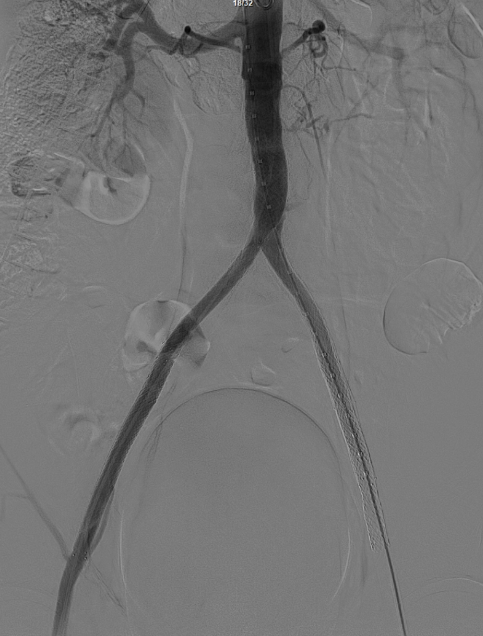

减容治疗

采用8F Rotarex导管对双侧髂动脉及腹主动脉下段进行减容处理。该器械对于陈旧性血栓具有良好的清除效果,且适用于支架内病变的治疗。减容治疗的主要目的在于获得理想的管腔空间,同时降低远端动脉栓塞的风险。

减容后造影显示仍存在重度残存狭窄,遂沿右侧股动脉置入VBX支架(直径11mm,长度59mm)。支架定位需满足近端完全覆盖腹主动脉病变段,远端距离双侧髂总动脉分叉至少1.5cm,以避免后扩张时大球囊对髂动脉造成损伤。

即时效果:造影显示腹主动脉、双侧髂总/髂外动脉及股动脉通畅。